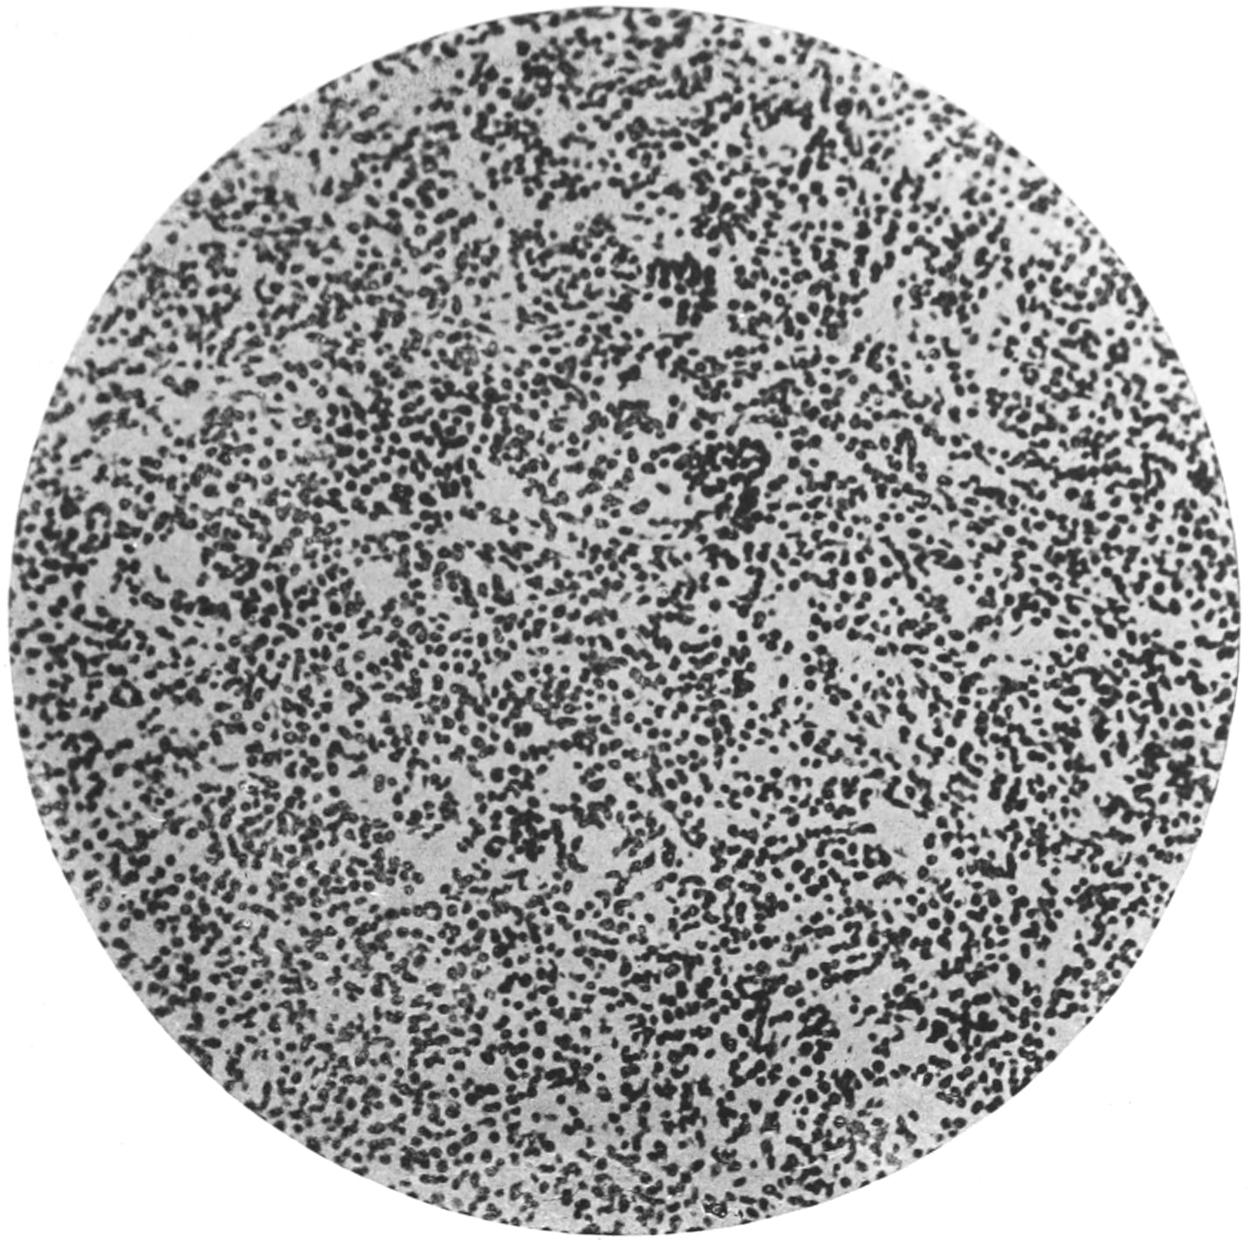

PLATE I

PLATE I.

BLOOD.

(Ehrlich triple stain.)

(Prepared by Dr. I. P. Lyon.)

Fig. I. TYPES OF LEUCOCYTES.

a. Polymorphonuclear Neutrophile. b. Polymorphonuclear Eosinophile. c. Myelocyte (Neutrophilic). d. Eosinophilic Myelocyte. e. Large Lymphocyte (large Mononuclear). f. Small Lymphocyte (small Mononuclear).

Fig. II. NORMAL BLOOD.

Field contains one neutrophile. Reds are normal.

The value of a careful blood examination is well illustrated by Plate I, prepared by Dr. Irving P. Lyon, in which are displayed the alterations of greatest interest to the surgeon.